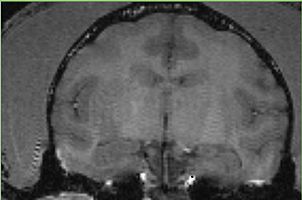

Valentino has structure not consistent with the normal anatomy Ron: this is likely a cyst.